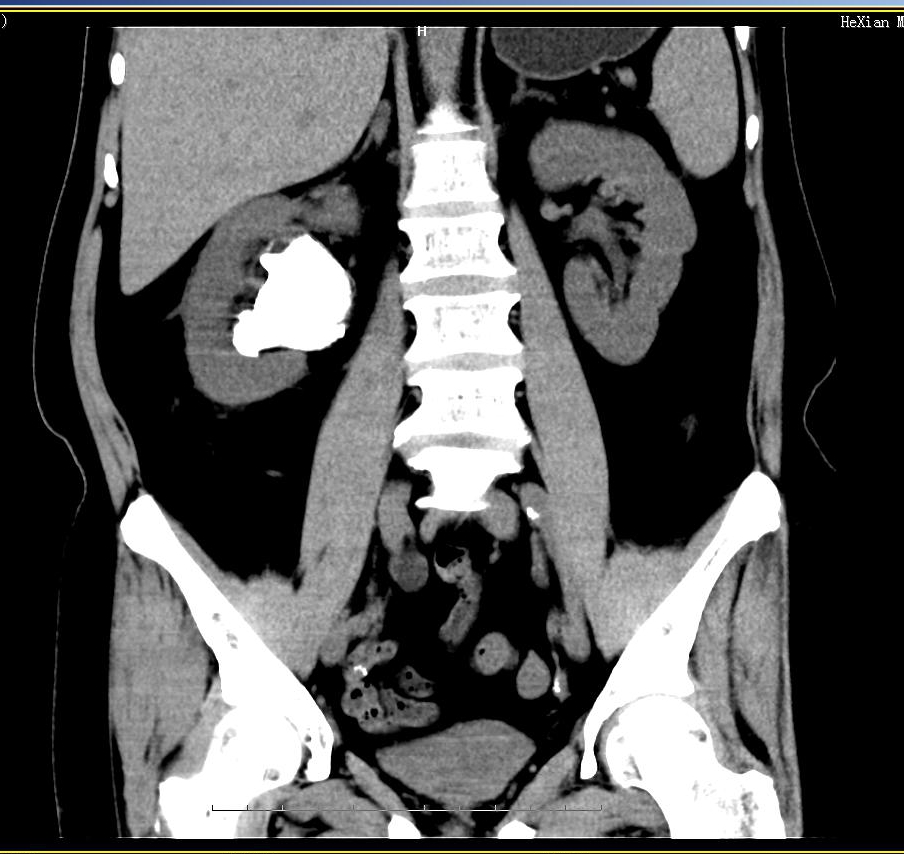

有朋友会有疑问,假如结石还在身体里面,怎么样能够进行分析呢?好啦,所以轮到我们的CT结石分析法出场了。

(2) CT分析法:利用CT扫描人体内各类结石不同参数,从而计算出结石的成分。